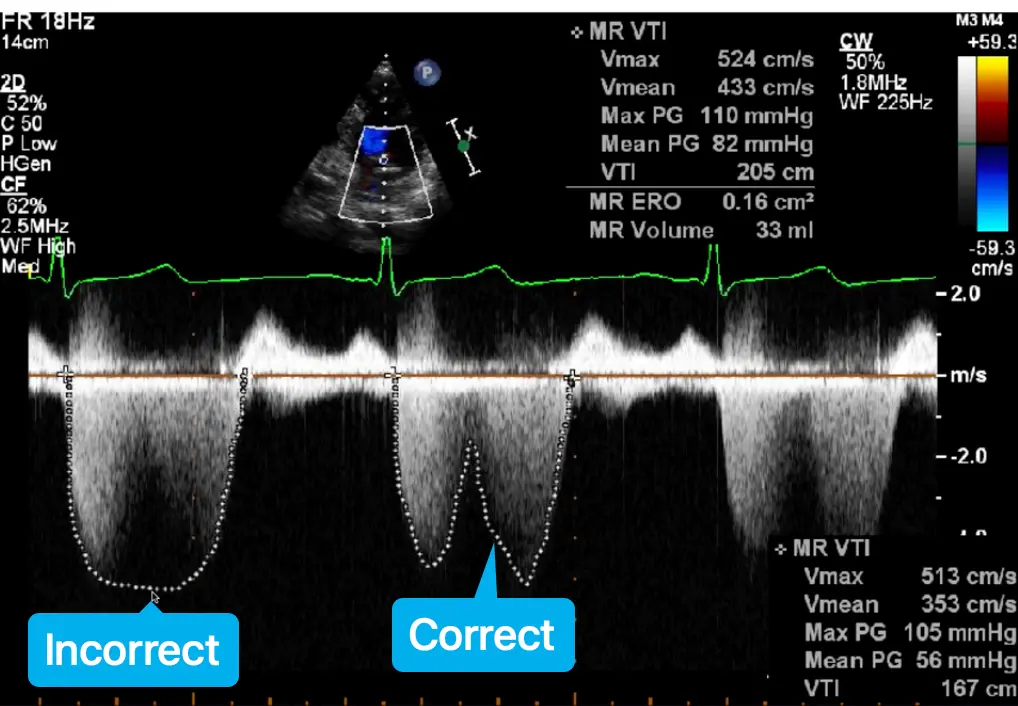

- Avoid overtracing the jet or turning up doppler gains to make the signal look holosystolic as this may overestimate the PISA

MR quantification in MVP

⛔ Avoid using single frame measurements - PISA EROA and VCW - when the MR is not holosystolic, e.g. MVP with late systolic MR, functional MR with biphasic MR, LV dyssynchrony with early systolic MR, as they can overestimate MR severity.

When non-holosystolic, you should use regurgitant volume (RVol) method.

Non-holosystolic MR

⛔ Avoid using single frame measurements - PISA EROA and VCW - when the MR is not holosystolic as they can overestimate MR severity.

When not holosystolic, you should use regurgitant volume (RVol) method.

- Examples of non-holosystolic MR include:

- MVP with late systolic MR

- functional MR with biphasic MR

- LV dyssynchrony with early systolic MR